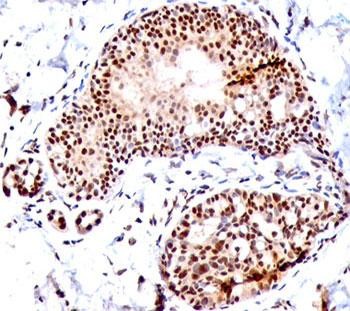

Product information "Anti-SUMO1, clone SM1/495"

0.2 mg/ml with 0.1 mg/ml BSA (US sourced), 0.05% sodium azide. This antibody is specific to SUMO1 and shows no cross-reaction with either SUMO2 or SUMO3. The small ubiquitin-related modifier (SUMO) proteins, which include SUMO1, 2 and 3, belong to the ubiquitin-like protein family. Like ubiquitin, the SUMO proteins are synthesized as precursor proteins that undergo processing before conjugation to target proteins. Also, both utilize the E1, E2, and E3 cascade enzymes for conjugation. However, SUMO and ubiquitin differ with respect to targeting. Ubiquitination predominantly targets proteins for degradation, whereas sumoylation targets proteins to a variety of cellular processing, including nuclear transport, transcriptional regulation, apoptosis and protein stability. The unconjugated SUMO1 protein localizes to the nuclear membrane. Protein function: Ubiquitin-like protein that can be covalently attached to proteins as a monomer or a lysine-linked polymer. Covalent attachment via an isopeptide bond to its substrates requires prior activation by the E1 complex SAE1-SAE2 and linkage to the E2 enzyme UBE2I, and can be promoted by E3 ligases such as PIAS1-4, RANBP2 or CBX4. This post-translational modification on lysine residues of proteins plays a crucial role in a number of cellular processes such as nuclear transport, DNA replication and repair, mitosis and signal transduction. Involved for instance in targeting RANGAP1 to the nuclear pore complex protein RANBP2. Covalently attached to the voltage-gated potassium channel KCNB1, this modulates the gating characteristics of KCNB1 (PubMed:19223394). Polymeric SUMO1 chains are also susceptible to polyubiquitination which functions as a signal for proteasomal degradation of modified proteins. May also regulate a network of genes involved in palate development. Covalently attached to ZFHX3 (PubMed:24651376). [The UniProt Consortium]

| Application: | WB, FC, IHC, IF |